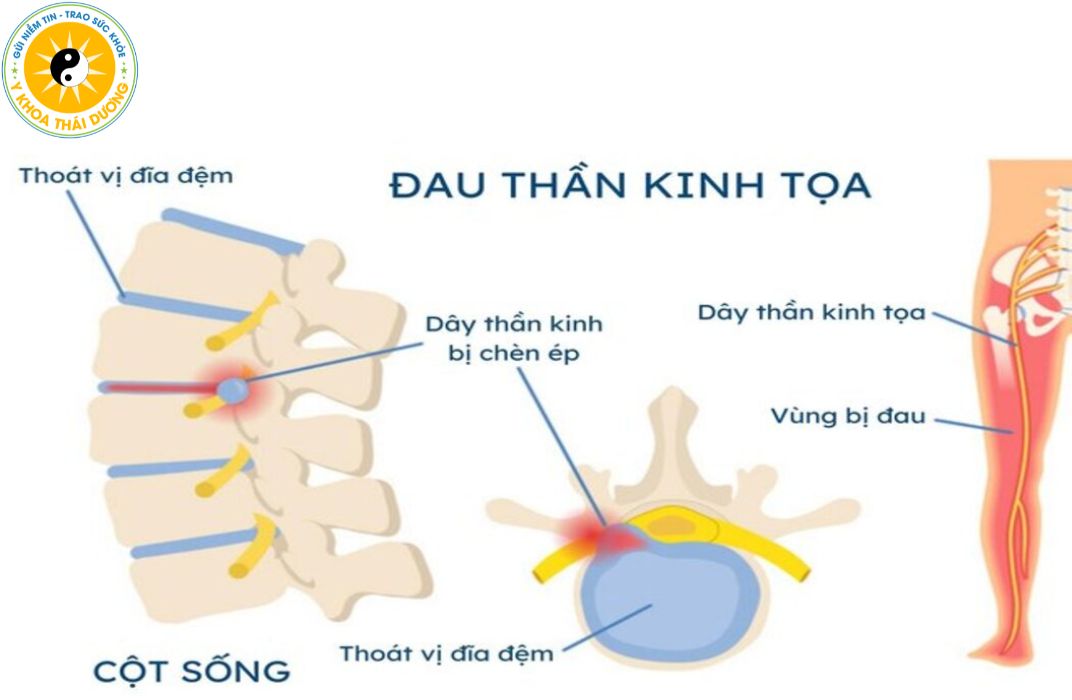

Đau thần kinh tọa: Cách nhận biết sớm và giải pháp điều trị chuẩn y khoa

Đau thần kinh tọa là tình trạng đau lan từ thắt lưng xuống mông và...